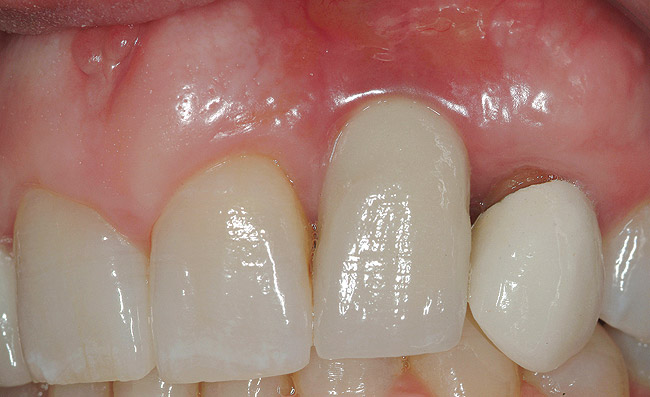

Figure 1  (Case 1) Initial presentation of restored implant No. 10.

Figure 1

The chief complaint of a 48-year-old woman who presented to her restorative dentist was, “I don’t like the way my implant looks” (Figure 1). This implant had been placed by a previous periodontist and restorative dentist. The patient is now seeking a second opinion. In evaluating this case upon referral to the periodontist, a reddened appearance of the gingival and mucosal tissue encompassing almost the entire facial aspect could be observed. In addition, the radiographs demonstrated a 5-mm diameter implant in place with a deciduous cuspid in the place of No. 11. Deep probing depths were noted around the facial aspect of the implant, and threads could be detected under the tissue.